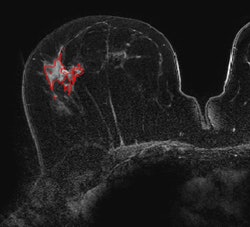

Breast DCE-MR images acquired on a 3-tesla scanner. Top, pure DCIS; below, invasive with DCIS; bottom, invasive cancer. Shown in these slices are the computer 3D lesion segmentation results. Images courtesy of Maryellen Giger, PhD.